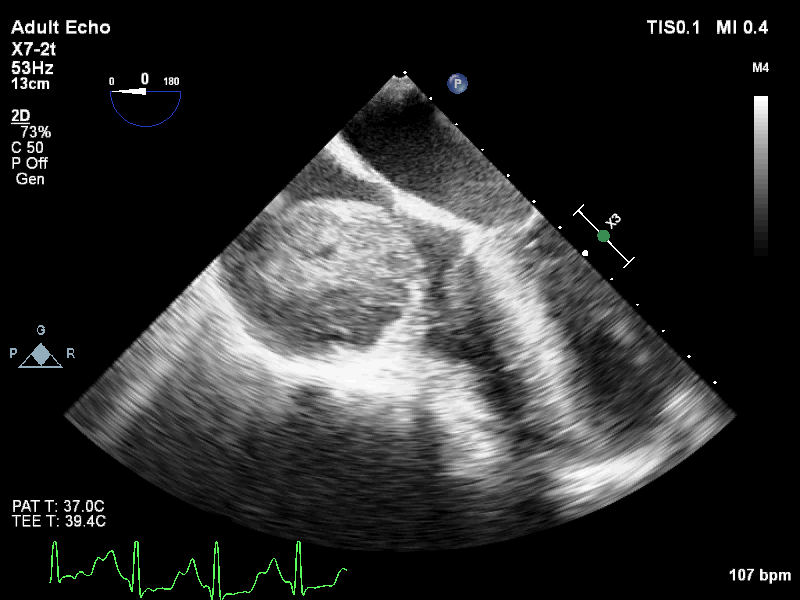

On further evaluation, the patient’s echocardiogram showed a 4.5 x 4.3 cm cystic tumor in the right atrium, hypertrophied obstructive cardiomyopathy with moderate left ventricular outflow tract obstruction, and good left ventricular function. She also underwent computed tomography (CT) and magnetic resonance imaging (MRI) of the chest, which revealed a neoplastic mass lesion, most likely right atrial myxoma.